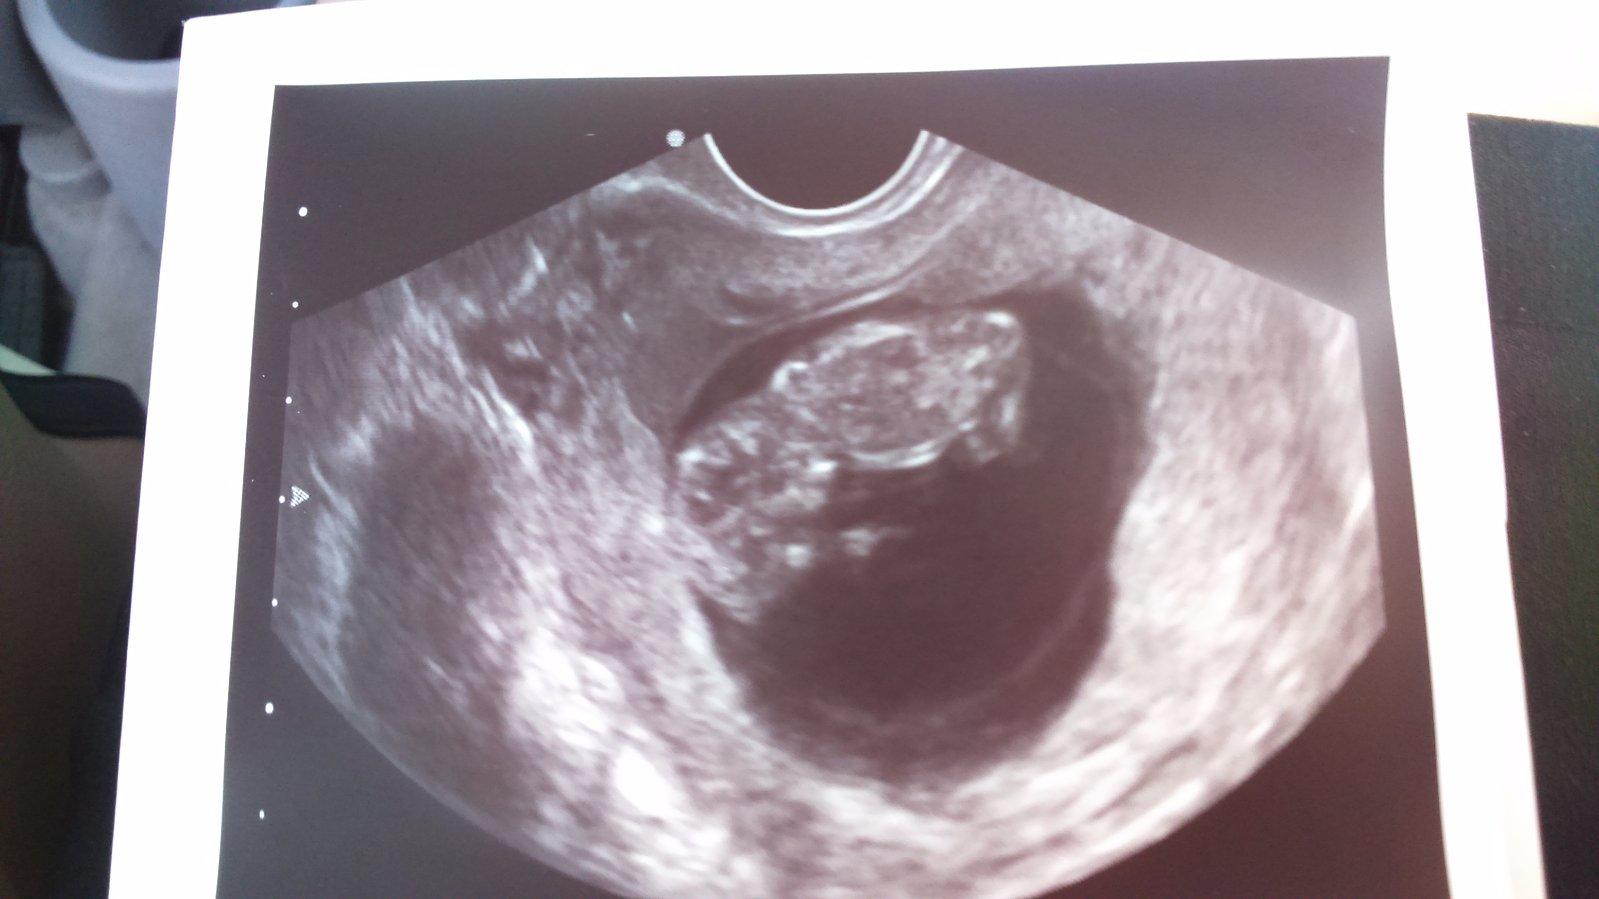

@matka295 Podla ovu je 10+1tt a podla lekara je 9+4. Viem to, lebo som jej pomahala urcit ovulku podla teplot.

@archanjel007 Ahoj. Viem, ze v tom @kotatko1234 mala chaos, ale drzala by som sa toho, co som jej vcera pisala. To presne sedi (rozdiel su 4 dni, co je pohoda). Ja som jej pomahala podla grafu urcit ovulaciu a aj sme sledovali spolocne testy. Ono, aj lekar sa mohol seknut, nakolko ratal od poslednej menstruacie. Ale tam jej jedna vynechala (alebo mala brutalne ppsunutu ovulku-to uz nezistime). Ale ked si zratam info o ovulke, tak to vyzera, ze tentokrat jej to lekar urcil presne. 😉

No podľa mňa nemôže ti podľa sona 26.4 namerat veľkosť plodu 6 + 4 keď bola 30.3 ovulka. veď veľkosť plodu sa na sone meria a do veľkosti plodu sa nezaratavaju dva týždne predovulacne čo si tu pisala. Veď sono vyráta týždne na základe veľkosti plodu.... toto mi vysvetli lebo ja buď som fakt tupa alebo nechápava .... Aj spolu s archanjel 🙄😏🤔